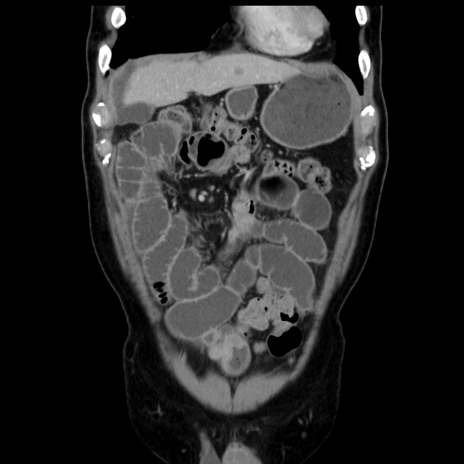

症例16(冠状断像)

【現病歴】 約1ヶ月前より間欠的に腹痛と嘔吐あり、当院消化器内科を受診したところCTで多発する肝臓のLDAを指摘され、精査中であった。以降は消化器症状は安定していたが、2日前より嘔気と腹痛があり、同日より排便・排ガスが消失した。改善認めず、 本日、救急外来を受診した。

【身体所見】意識清明・会話良好、BT 36.3℃、BP 127/80mmHg、 P 80bpm、腹部:膨満あり、平坦・軟、上腹部正中および下腹部正中に圧痛あり、反跳痛なし、筋性防御なし。

横断像